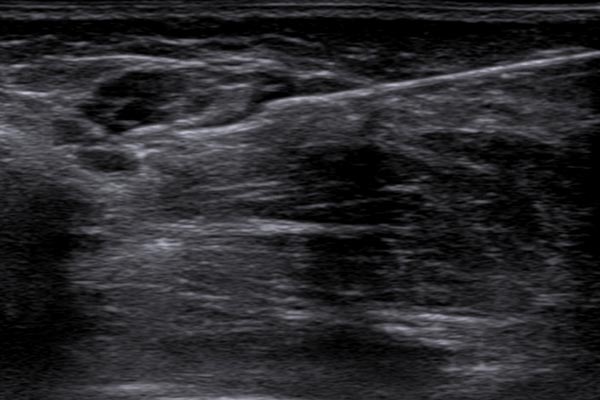

Die Biopsie erfolgte in gleicher Sitzung ultraschallgesteuert mit einer Einmalbiopsiepistole. Die Biopsienadel wird mit einem Federsystem ca. 2 cm in das Gewebe „geschossen“ und über eine kleine Einbuchtung in der Nadel ein kleiner Gewebezylinder von wenigen Millimetern Dicke und knapp 2 Zentimeter Länge gewonnen. Wenn der Zielort dieser sehr kleinen Gewebeprobe gut gewählt wurde, ist hier eine histopathologische Beurteilung sehr gut möglich ohne größere Verletzung.